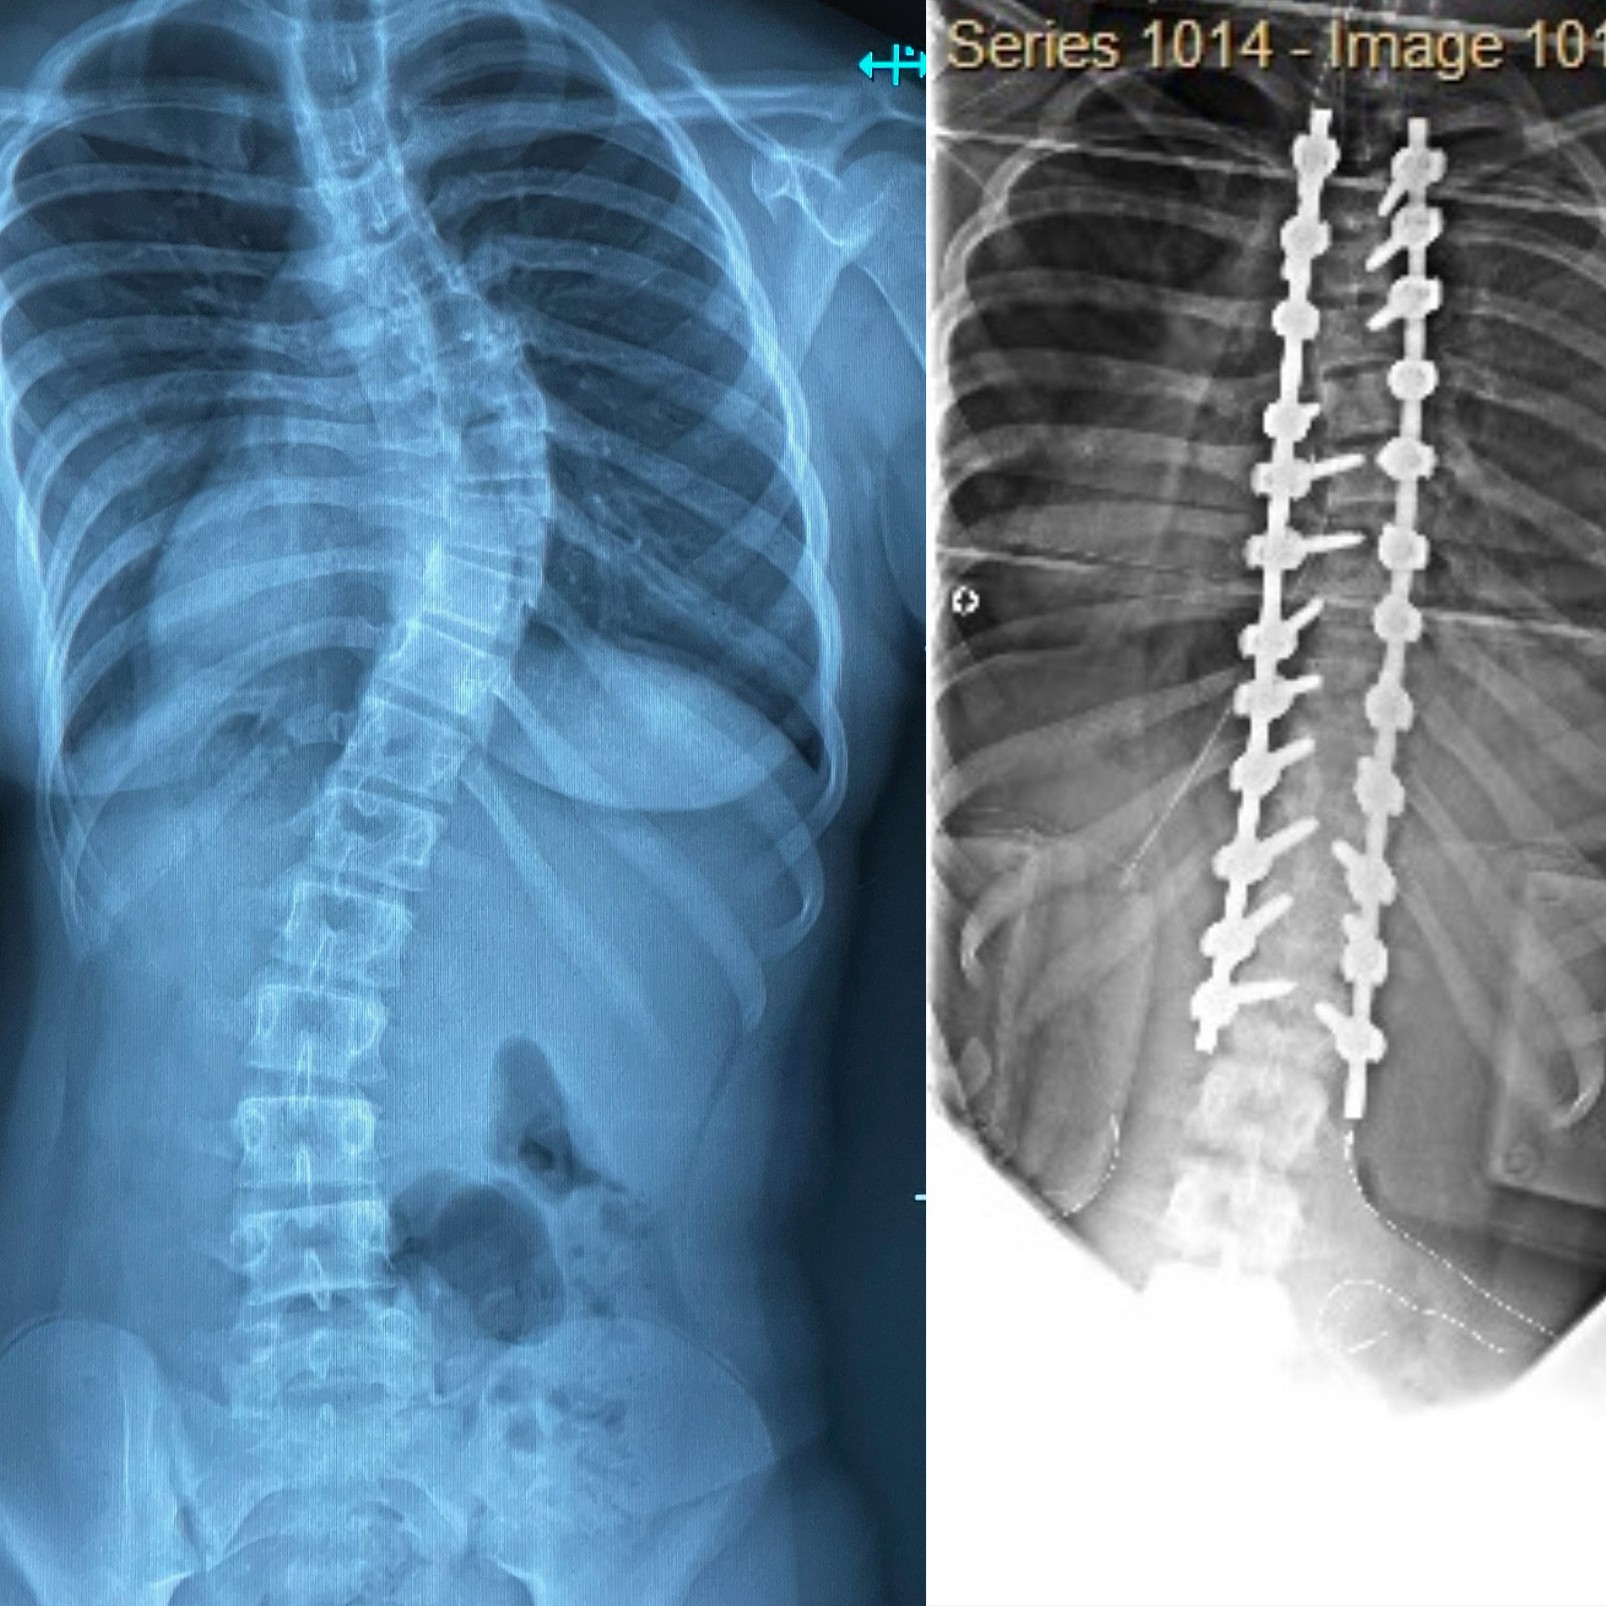

After X-rays, I was told I had about a twenty-three degree curve- mild enough not to panic, but serious enough to keep an eye on. A few months later, it had worsened slightly, and I was fitted for a brace. I wore it every night for about four or five months. I kept dancing. I went to school. Everything stayed the same. Nothing seemed severe- until it did.

When I went back to the doctor, they took new X-rays, and when the physician pulled them up on the screen, he gasped. My curve had jumped from the twenties to the fifties in just a few months. The brace wasn’t helping anymore.

My curve had now reached sixty-three degrees. The doctor said if we didn’t act soon, I’d live a life of pain. I don’t think I fully understood what was happening. I remember thinking, ‘Cool, I’m getting surgery! My friends can visit me in the hospital, I’ll get gifts, and I’ll have a story to tell.’ I didn’t fully comprehend that they were about to put metal rods inside my spine.

Since my surgery, I have come to realize many things, one specifically: scoliosis surgery isn’t like other surgeries. In most surgeries, doctors remove or fix something to make you feel better. But in this one, they completely rearrange your spine- the center of who you are- and your body is forced to relearn how to live with it. It’s scary and invasive, but it’s also life changing.